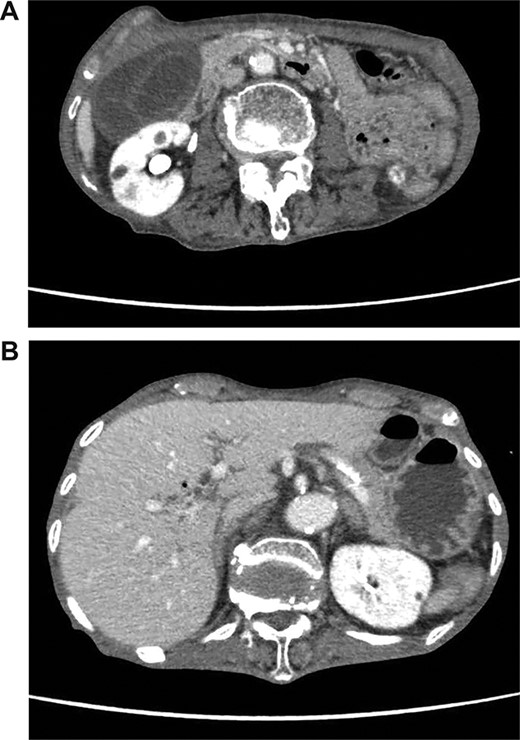

On admission, her vital signs were normal. Her medical history included dermatomyositis, hypertension and osteoporosis. She had a white blood cell count of 10.6 × 103/μL, hemoglobin of 8.2 g/dL and lactic acid of 0.8 mmoL/L. A physical examination demonstrated strong tenderness in her right upper quadrant abdomen. Ultrasonogramphy (US) showed diffuse wall thickening of her gallbladder without cholecystolithiasis. US also revealed small mobile echogenic foci moving inside the portal venous branches (Fig. 1). The hyperechogenic foci were seen in the middle segment and right anterior segment of the liver. Contrast-enhanced computed tomography (CT) showed a diffusely thickened wall of the gallbladder with poor enhancement, suggesting acute necrotizing cholecystitis (Fig. 2). Tiny bubbles were seen in the intrahepatic portal venous branches (segment 4 and segment 5), but there was no evidence of bowel ischemia. She was then diagnosed with necrotic cholecystitis and immediately underwent emergency operation.

(A) Abdominal CT shows a poorly enhanced and thickened wall of the gallbladder. (B) Abdominal CT shows tiny bubbles in the intrahepatic portal venous branches.